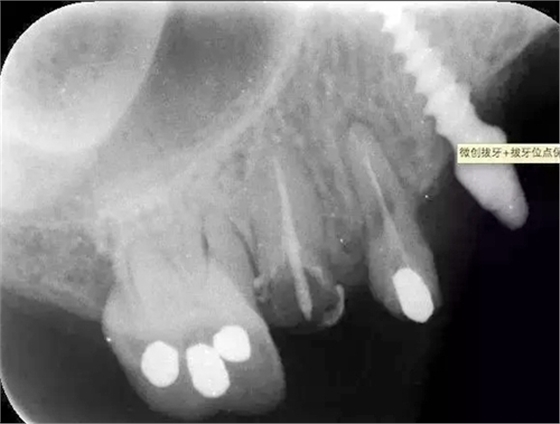

檢查:14根面旁穿,無法保留,15根長不足。

處理:14、15微創(chuàng)拔牙+拔牙位點保存術(shù)。

?術(shù)前的x線根尖片